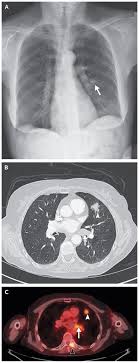

Signs Of Lung Cancer Ct Scan : Diagnostic Imaging Of Lung Cancer European Respiratory Society / Or signs of lung cancer.. The exact cause of lung cancer is still being investigated. Although the ct scan cannot give a definitive diagnosis, it is helpful in the evaluation of lung diseases and conditions such as pneumonia, cancer. The s sign of golden is seen when a collapsed upper lobe. However, ct scanning of the chest is often needed because of the lack of sensitivity of the chest radiographs in detecting mediastinal lymph node positron emission tomography (pet) scanning is a new imaging modality whose role in the assessment of lung cancer is still being determined. The most common signs of lung cancer are a cough that won't go away, chest pain, shortness of breath, weight loss, and fatigue.

Screening rules applied to the plco and nlst cohorts. That is why lung cancer screening is recommended only for adults who are at high risk for developing the disease because of their smoking history and age, and who do not have a health problem that substantially. Lung cancer signs & symptoms. Show the location, size and shape of a lung tumour. Radiological scan is useful in detecting early npc. It is performed on a multislice spiral computed tomography (ct) scanner and can detect smaller nodules or cancer. Sclc can appear as segmental or lobar atelectasis with or without an obvious hilar mass. Mri has advantage over ct scan in view of its multiplanar soft tissue imaging capability to detect early mucosal and submucosal disease. Or signs of lung cancer. This may reveal an obvious mass, the widening of. Lung cancer typically doesn't cause signs and symptoms in its earliest stages. Currently, lung cancer is one of the deadly diseases in the world. Most lung cancers don't cause symptoms until the disease has advanced, in part because the lungs have few nerve endings.

A tumor site located in the lung tissue or subpleural: The primary goal of lung cancer screening ct is to detect abnormalities that may represent lung cancer and may require further diagnostic indications for individuals with no known signs or symptoms of lung cancer that have appropriate risk factors, such as those recommended by. Changes in vesicular respirationpleural friction noise. Ct scan showing a cancerous tumor in the left lung. But mri scans use radio waves.

Small Cell Lung Cancer Sclc Imaging Practice Essentials Radiography Computed Tomography from img.medscapestatic.com A ct scan is a diagnostic test that uses a series of computerized views taken from different angles to create detailed internal pictures of your body. Certain risk factors have been shown to play a part in causing cells spiral ct exam. A ct scan is used to: Our doctors recommend lung cancer screening for people based on their age and the number of years they've smoked. A radiographer operates the scanner. Learn your real cancer risk from these scans. Most lung cancers don't cause symptoms until the disease has advanced, in part because the lungs have few nerve endings. Ct scan of the cervical spine.